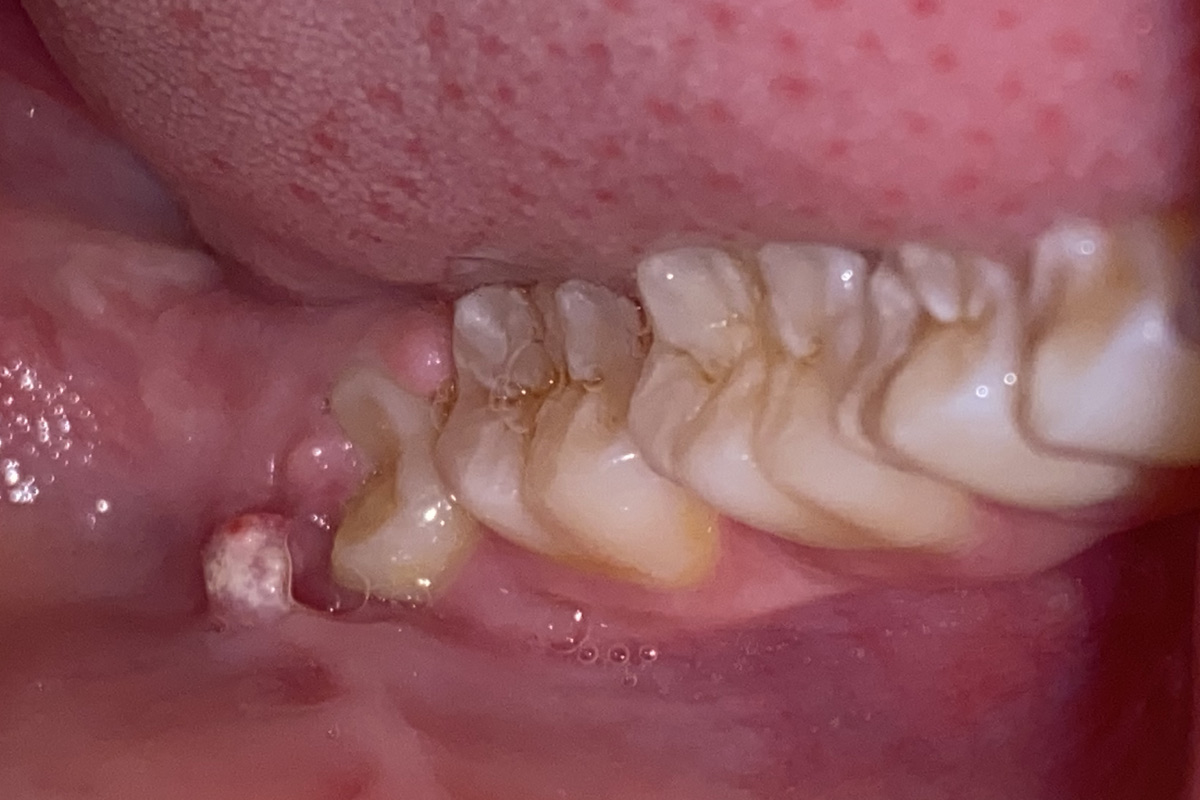

जब अक्लदाढ़ आती है तब तक मुॅह में सारे सारे दांत एवं दाढ़ आ चुके होते हैं इसलिए उनके लिए जगह (स्पेस) बहुत कम रहता है अतः अक्लदाढ़ या तो पूरी तरह से आती (fully impacted) ही नहीं है या टेढी-मेढी आती है अथवा आधी-अधूरी (partially impacted) आकर रह जाती है जो कि परेशानी का कारण बनती है |

आजकल की युवा पीढ़ी में अक्लदाढ़ या तो आती ही नहीं है (मतलब हड्डी अथवा मसूड़े में दबी रह जाती है अथवा आधी-अधूरी या टेढी-मेढी आती है | इस का मुख्य कारण हमारा आधुनिक खानपान है जिसकी वजह से हमारे जबड़े का आकार शनैः शनै छोटा होता जा रहा है|

सामान्यतया अक्लदाढ़ को निकालना ही बेहतर होता है क्योंकि कि यह मुख गुहा(ओरल केविटी) में सबसे अंत में स्थित होने के कारण यहाँ तक ब्रश पहुँचना मुश्किल होता है और अगर ब्रश पहुँच भी गया तो अच्छे से सफाई करना नामुमकिन होता है जिससे कि बार- बार संक्रमण होने की संभावना रहती है | आंशिक रूप(partially impacted) से निकली दाढ़ में संक्रमण की संभावना ज्यादा होती है क्योंकि वहाँ अक्लदाढ़ एवं मसूड़े के बीच में एक पॉकेट बन जाती है जिसमें खाना फंसा (food lodgement) रह जाता है जो की संक्रमण का मुख्य कारण होता है| जिस की वजह से दन्त छय(dental decay) एवं अक्लदाढ़ के चारों ओर के मसूड़े में संक्रमण (pericoronitis) हो जाता है